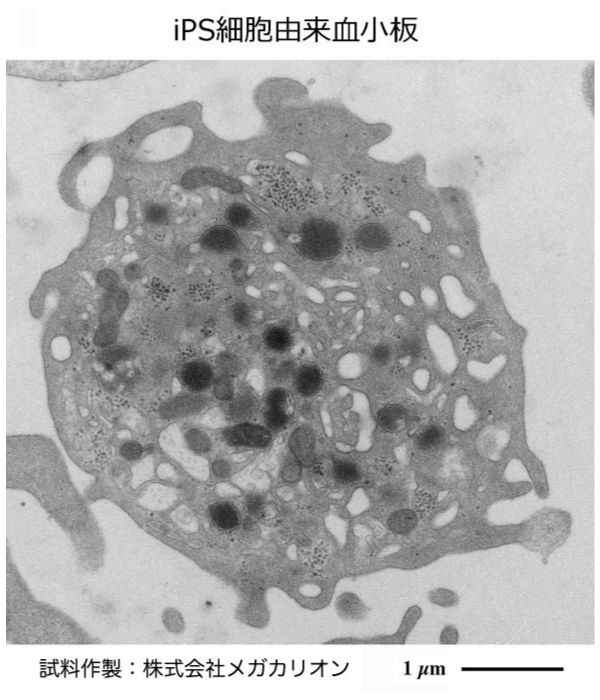

透過型電子顕微鏡 細胞. 透過型電子顕微鏡 試料作製プロトコール Bio-Medical Sample Preparation for TEM Observation 透過型電子顕微鏡の試料作製プロトコールを紹介します。. 透過電子顕微鏡(Transmission Electron Microscope:以下TEM と略記)は光学顕微鏡(以下光顕と略記)と同様に試料の拡大投影像を得るための装置である。 その拡大倍率範囲は、数十μmサイズの細胞全体の観察(数百倍)からサブnmの原子配列構造観察(数百万倍. これまで電子顕微鏡による三次元観察は、透過電子顕微鏡(TEM)によるTEM tomography法によって行われてきた。近年、コンピューター技術と走査電子顕微鏡(SEM)の性能が向上したことにより、SEMを用いたFIB-SEM法、Serial Block-face SEM(SBF-SEM)法、Array tomography法といった三次元観察手法が注目されている。.

日本電子 透過型電子顕微鏡 jem-1400作例 『生物学の基礎 -生き物の不思議を探る-』. 電子顕微鏡について 電子顕微鏡とは、高真空に保たれた顕微鏡の鏡筒 内において、電子銃で電子を加速した電子線を作り、 これを観察したい対象にあてて透過の程度によって 濃淡をつけ、対象の形態を拡大観察する顕微鏡のこ とである。. デジタル大辞泉 - 透過型電子顕微鏡の用語解説 - 電子顕微鏡の一。試料に電子線を照射し、透過した電子線を磁場で屈折する電子レンズを用いて拡大・結像させる。光学顕微鏡に比べ分解能が極めて高く、0.2ナノメートル程度。細胞やウイルス内部の微細構造の観察に適している。.